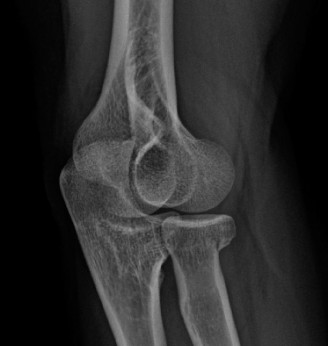

The correct answer is (C). Although pectoralis major muscle (PMM) injuries are

primarily diagnosed clinically, MRI is the imaging modality of choice to evaluate a PMM tendon injury. The extent and location of the injury can many times be assessed with MRI. The Tietjen’s classification system can be used for PMM injuries. Type I is a contusion or sprain. Type II is a partial tear. Type III injuries are complete tears and further classified by anatomic location: III-A (muscle origin), III-B (muscle belly), III-C (musculotendinous junction), III-D (tendinous insertion). Further subclassification were suggested including III-E (bony avulsion from the insertion) and II-F (muscle tendon substance rupture). Type II and Type III injuries have been reported at rates of 9% and 91%, respectively. Among complete tears, type III-D has been reported as the most common (65%). Ultrasound is a reasonable alternative to MRI, particularly if its use means avoiding delay of surgical repair. Ultrasound is much more user-dependent. CT will not allow adequate soft tissue evaluation. Further radiographic evaluation is incorrect because a radiograph of the injured shoulder has already been obtained. The radiographic findings are often normal, but the clinician should look for bony avulsions. The characteristic findings on radiographs are soft tissue swelling and absence of the PMM shadow.

After evaluating the MRI, the patient is diagnosed with a complete rupture of the pectoralis major tendon (Fig. 2–79). What is the recommended first step in management?

Figure 2–79